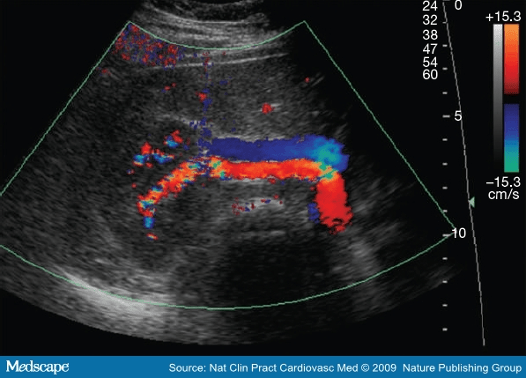

Determine whether this flow pattern is normal or abnormal

What is Abnormal?